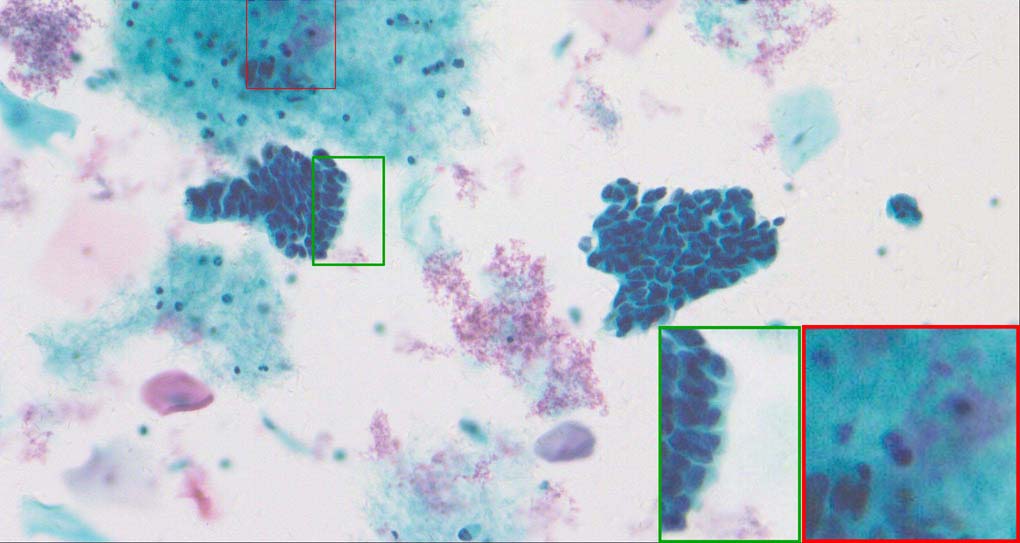

To demonstrate the effectiveness and efficiency of the proposed image fusion method , we conduct a set of comparative experiments on three image datasets. The first is composed by 8 pairs of multi-modal medical images and the second one contains 15 pairs of multi-focus gray or color natural images. These two datasets are often used in many related papers and some examples are shown in Figure 3(a) and Figure 3(b). The third one is a new multi-focus cervical cell image dataset collected by ourselves, which consists of 15 groups of color images and each group contains a series of multi-focus cervix cell images with size of or , etc. Some source examples are shown in Figure 3(c). Our source code implemented in C++ along with the new multi-focus cervical cell image dataset is available online.

Figure 9, Figure 10 and Figure 11 show the comparative fused results of the multi-focus cell images shown in Figure 3(c). For clarity, we also present a closeup view in the right-bottom of each sub-picture in Figure 9 and Figure 10. As shown in the close-up views of Figure 9, the fused images based on DSIFT, IM, MWGF and BF methods are extremely blurred in the boundary and fail to keep the details of cell nucleus. Furthermore, the DTCWT and NSCT based methods produce halo artifacts in the fused images, while GFF and CNN based methods fail to preserve the small cell nucleus. LP-SR based method nearly works fine which keeps the most of the details of the small size cells, but the integrity of the clustered large size cells is damaged. Fortunately, in our proposed method, the integrity of the clustered large size cells is preserved and most of the isolated small size cells are maintained from the original images, which demonstrates the best visual quality.

Similarly, as shown in the close-up views of Figure 10, the fused images from DSIFT, IM, MWGF and BF are blurred and lose some nucleus details, while the results from DTCWT, GFF, CNN and NSCT produce halo artifacts. LP-SR based method can keep details well but also produces halo artifacts and other noise. Our method can preserve the focused areas of different source images well without introducing any artifacts. For the example illustrated in Figure 11, the fused images generated by DSIFT, DTCWT, IM and NSCT all fail to preserve the focused areas of different source images and result in extremely blurred images. The GFF, CNN, MWGF and BF based method introduces a lot of color distortion of the nucleus regions and the obvious halo artifact. The result of LP-SR based method is close to the one of our method but introduces some odd color distortion. Again, our method produces fused image which can preserve the focused areas of different source images well without introducing any artifacts.